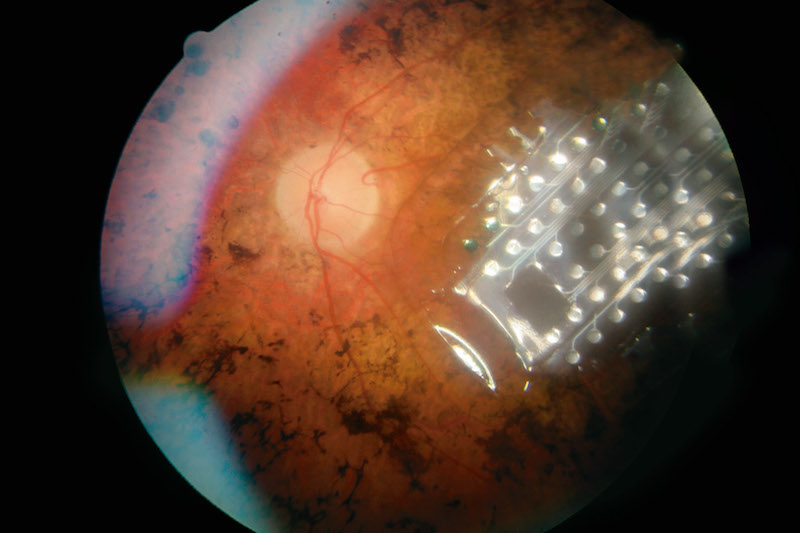

En su intervención, Nadal ha dado detalles sobre “la visión artificial, una realidad que ha llegado

antes de tiempo” y que se basa en dos tipos de implantes retinales (Argus II y Alpha IMS). En la actualidad, hay cuatro personas implantadas en España y en el mundo la cifra sube hasta los 150. Con el propósito de que “las personas invidentes puedan recuperar la visión”, se empezó a trabajar en estos dispositivos como “una manera de engañar al cerebro para que pueda identificar un estímulo como visión y que ésta se corresponda con una visión real, aunque algo somera”, ha explicado el oftamólogo.